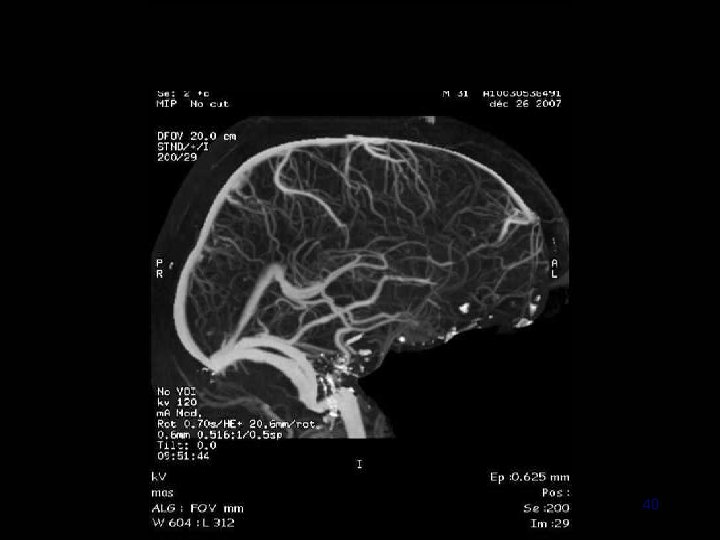

40

41

IRM • Diagnostic: – Sagittales T 1 en SE +++ – Coronales T 2 ou Flair – Axiales T 2 EG ++ +/- Coronales T 1 sans et avec Gado • Extension (et suivi) : ARM veineuse – – Contraste de phase 3 D PC Temps de vol 2 D TOF veineux Acquisition volumique +Gd ARM dynamique 42

Angio IRM (ARM) 3 D PC 2 D TOF veineux 3 D Gd+ 58

• 2 D TOF veineux – Rapide – C– Faux + • 3 D Gd + – Rapide ++ – Sinus et veines corticales 60

Conclusion La séquence d’ARM 3 D dynamique Fournit des images de bonne qualité Imagerie parallèle : résolutions temporelle et spatiale Permet une évaluation du système veineux cérébral Acquisition rapide ( 2 minutes ) En concordance avec les autres séquences Informations dynamiques Séquence ARM de référence au diagnostic La seule au suivi ? 71